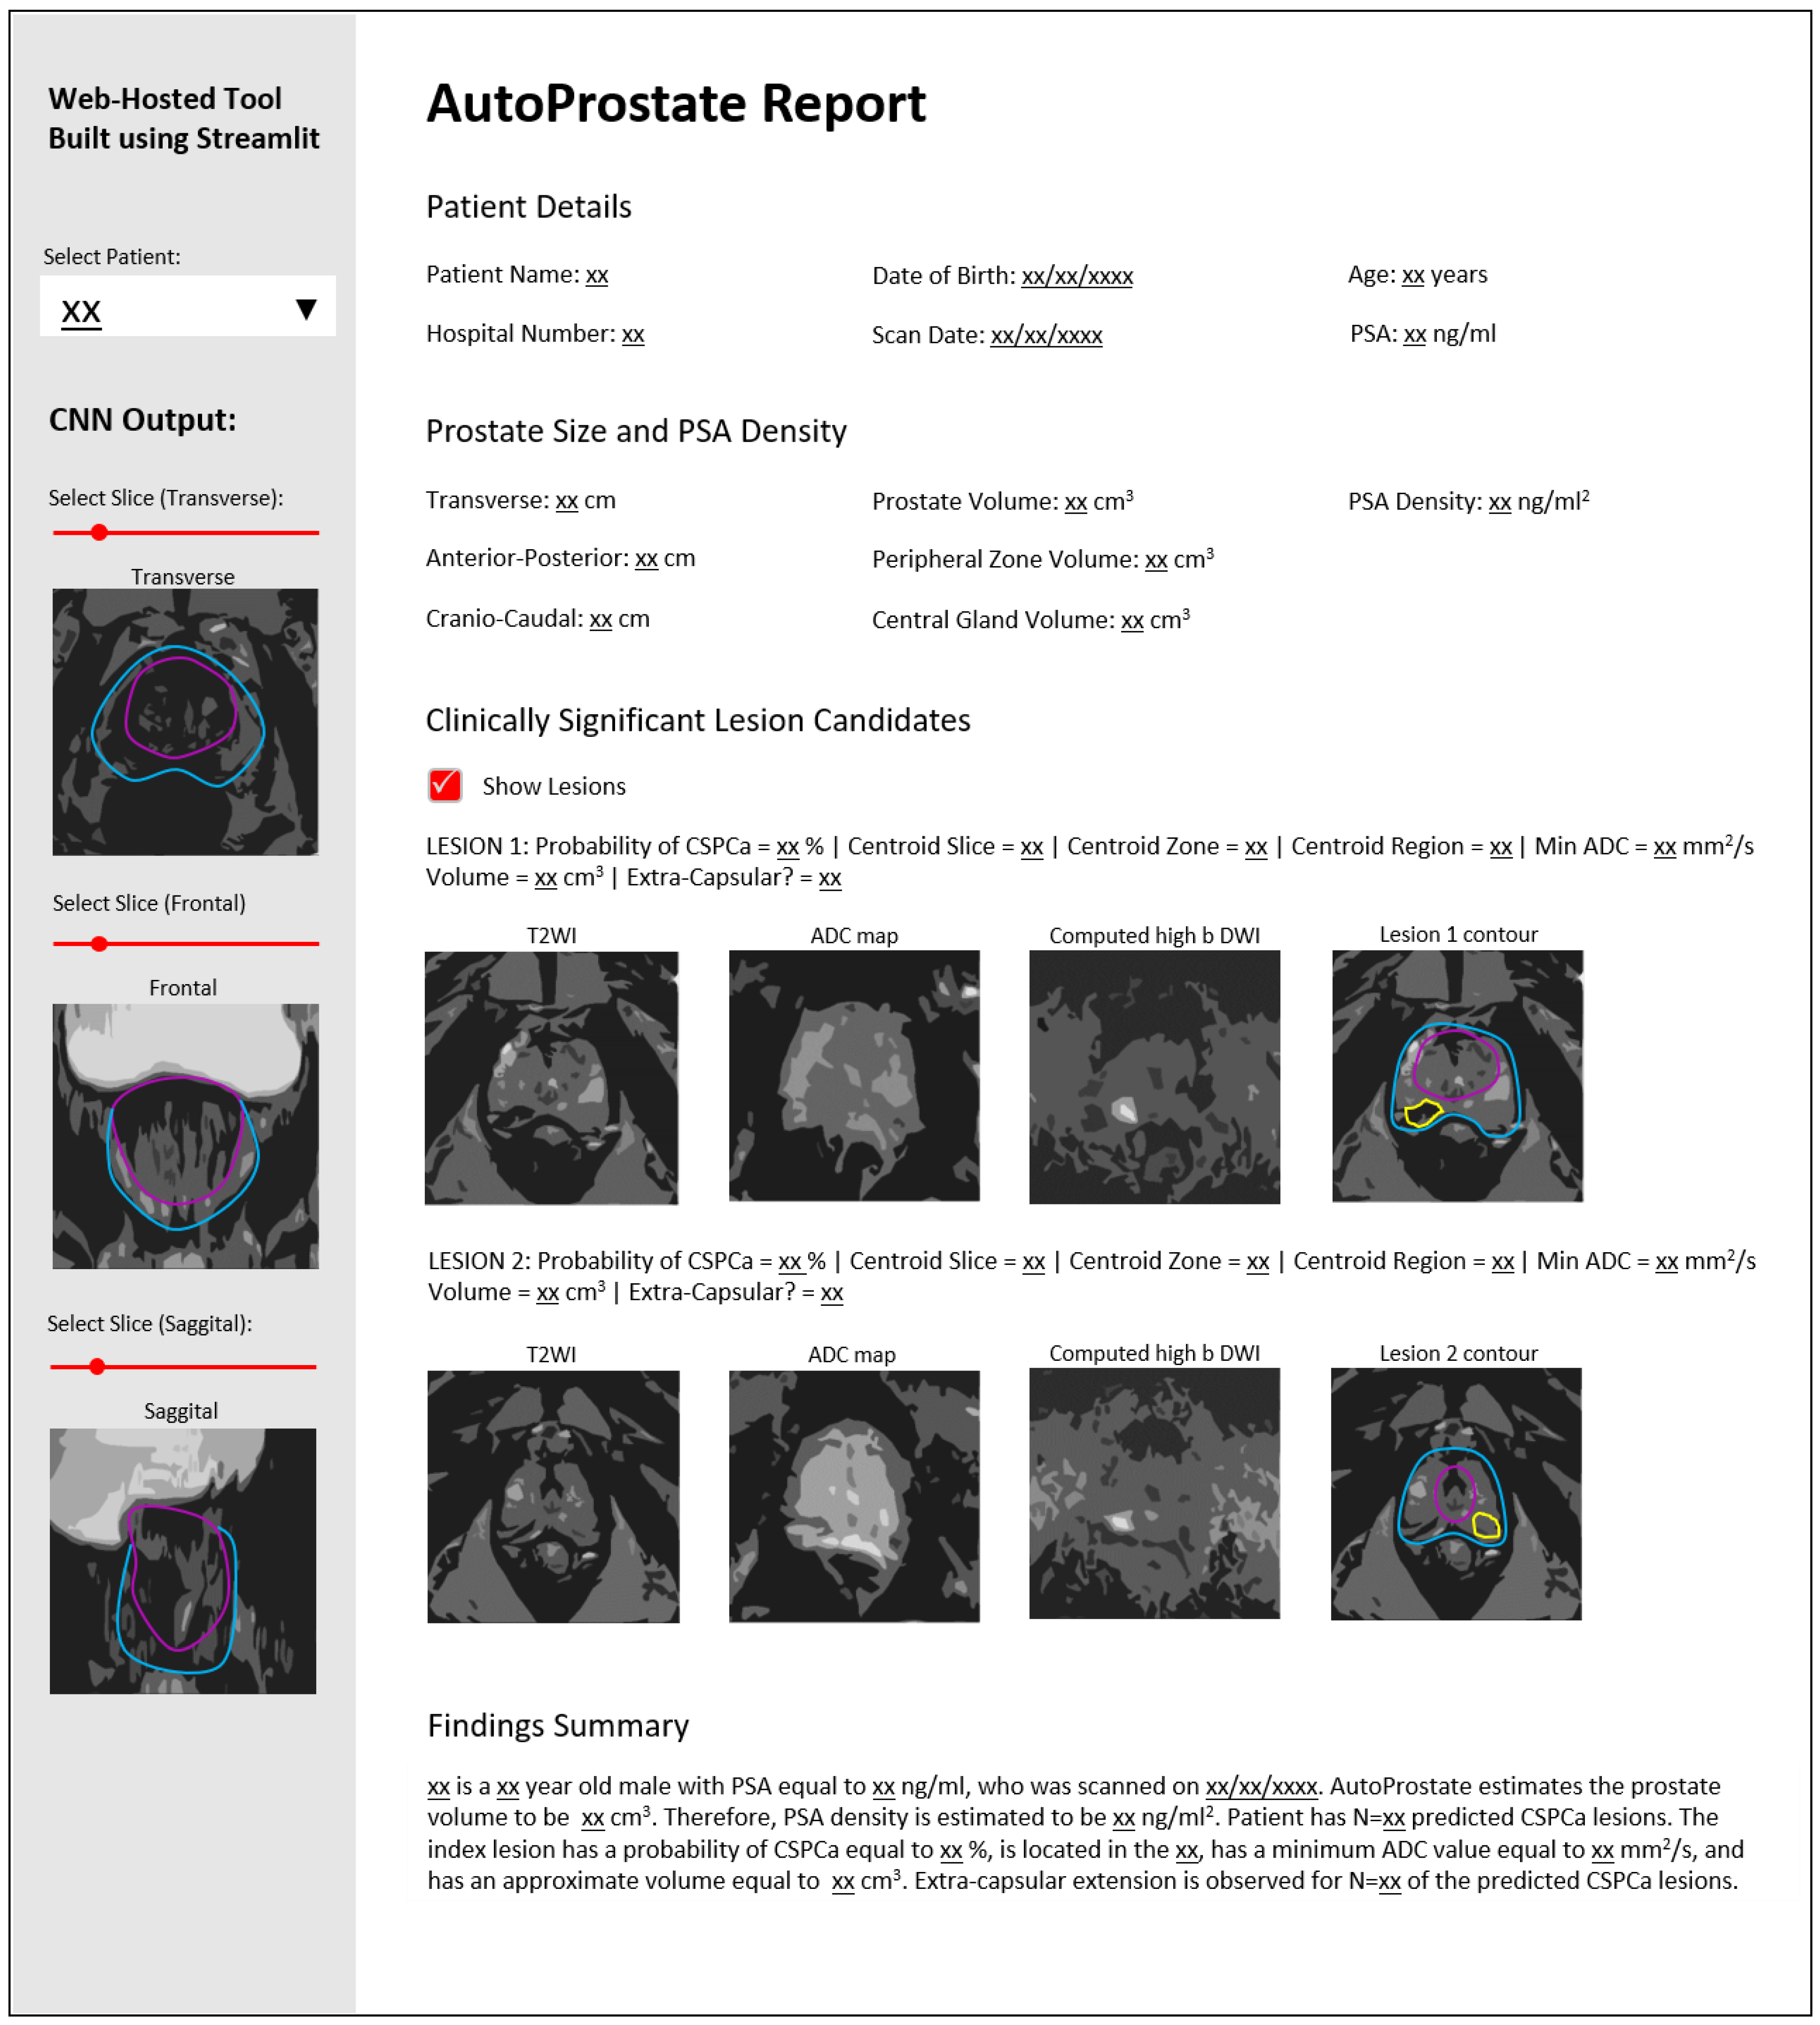

2.3. Report-Generator Module